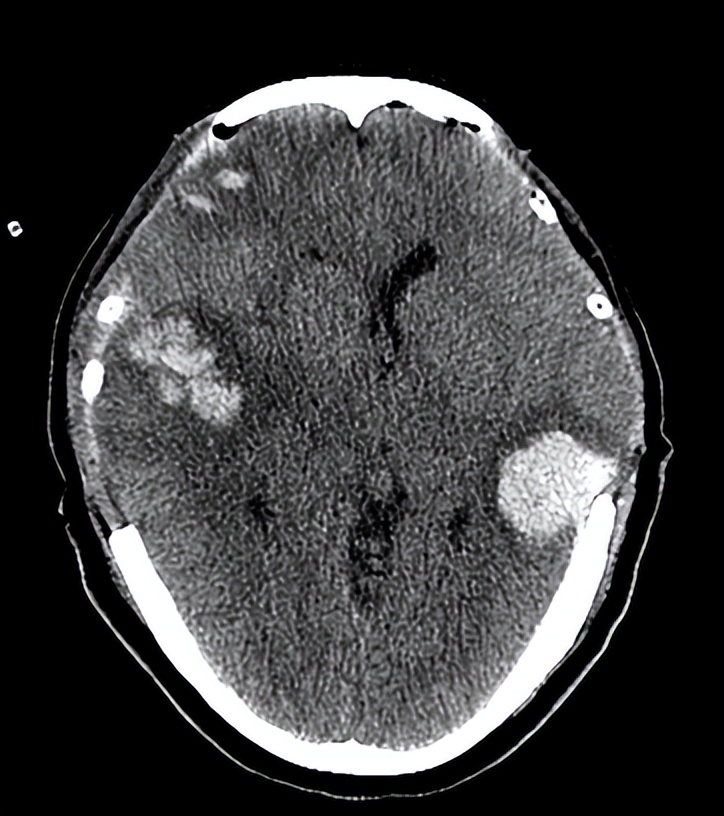

06-07 21:30术后复查头CT示: